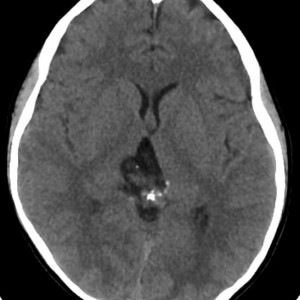

CTです

左のCTでは低密度の松果体腫瘍とまばらな石灰化がみられます。右の造影CTでは,腫瘍のごく一部が増強されます。 この時点で,低吸収で石灰化があるので類皮のう胞 dermoid cystを強く疑います。dermoid cystを主体とする混合性胚細胞腫瘍 mixed germ cell tumorも候補です。あるとすれば,germinomaかteratomaです。